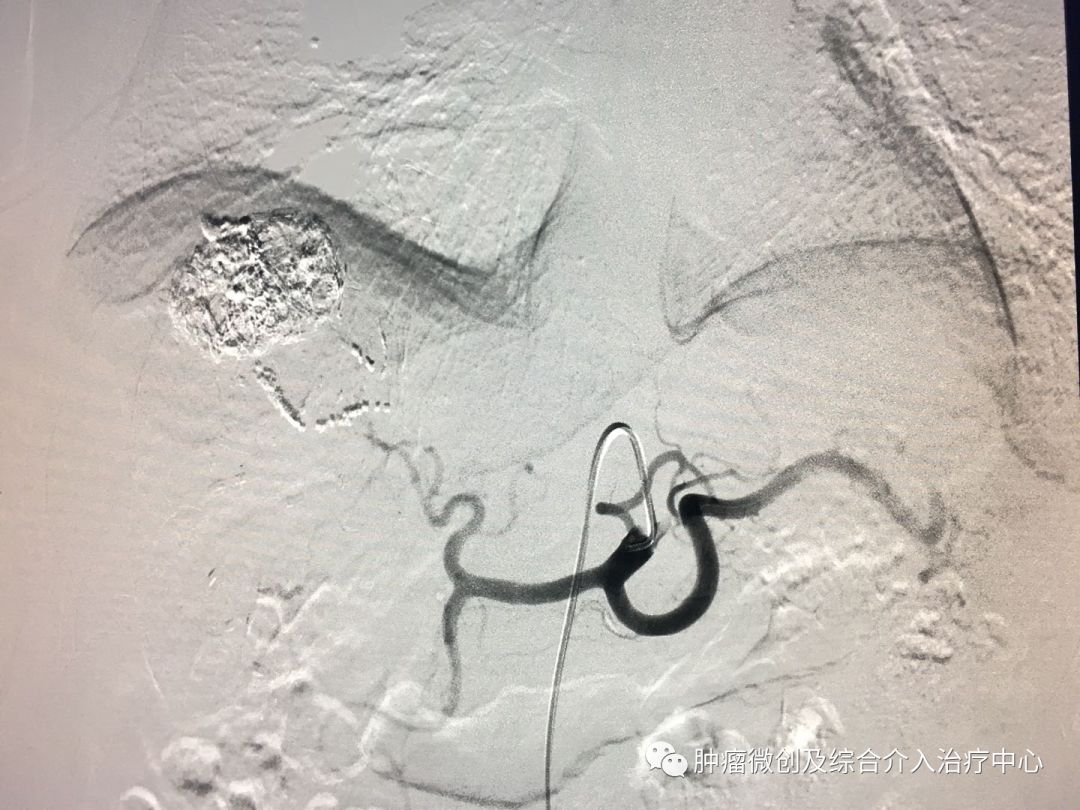

(肝静脉-门静脉穿刺成功,门脉高压,门静脉扩张明显)

运城第一医院肿瘤介入科专家,运城市第一医院介入科专家

(肝静脉-门静脉支架置入搭桥术,分流门脉部分血流,门脉压力降低)